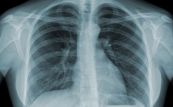

Các triệu chứng phổ biến nhất của COPD là khó thở, sản xuất đờm quá mức, và ho mãn tính. Hình ảnh trên phim chụp x quang ngực gợi ý chẩn đoán bệnh phổi tắc nghẽn mạn tính (COPD). Để hiểu rõ về hội chứng này mời các bạn cùng tham khảo bài viết Bệnh phổi tắc nghẽn mạn tính (COPD) trên x quang.